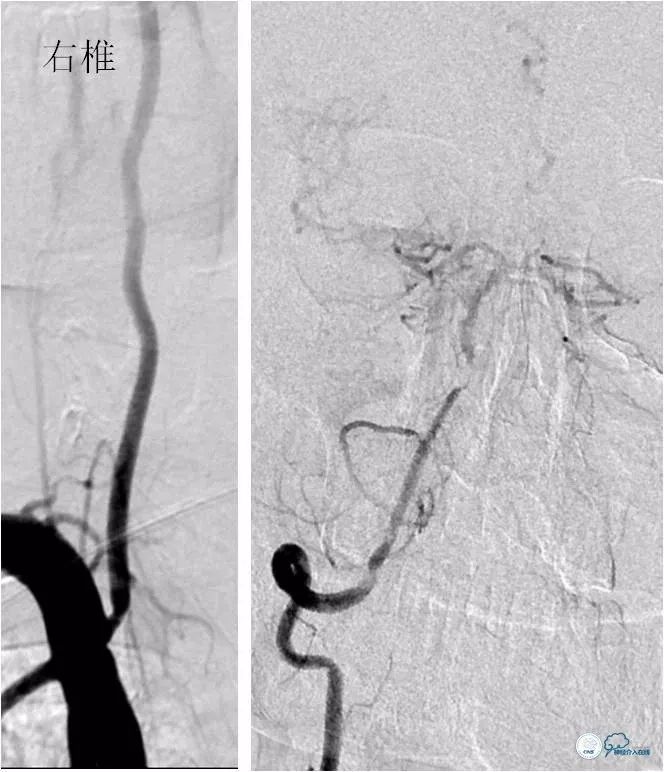

DSA:左椎动脉优势,左椎动脉V1段重度狭窄,右椎动脉V1段中度狭窄,双椎动脉V4-基底动脉下段重度狭窄,狭窄率约为85%,狭窄段有AICA发出,双侧后交通动脉未开放(图6-9)。

图6

图7